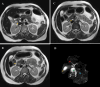

Figure 2. Serial MRCP films showing annular pancreas (A-D)

MRCP: Magnetic resonance cholangiopancreatography (A) MRCP (T2 image/transverse cut): White arrow indicates the main pancreatic duct (MPD); yellow arrow indicates the encircling pancreatic parenchyma. (B) MRCP (T2 image/transverse cut): Yellow arrow indicates the MPD encircling the duodenum. (C) MRCP (T2 image/transverse cut): White arrow indicates the relation of MPD in relation to the common bile duct (CBD) indicated by the yellow arrow. (D) Reconstructed MRCP image showing the annular pancreas where the red arrow indicates right hepatic duct (RHD), yellow arrow indicates the gall bladder, green arrow indicates the common bile duct (CBD), white arrow indicates the annular pancreatic duct, and blue arrow indicates the MPD